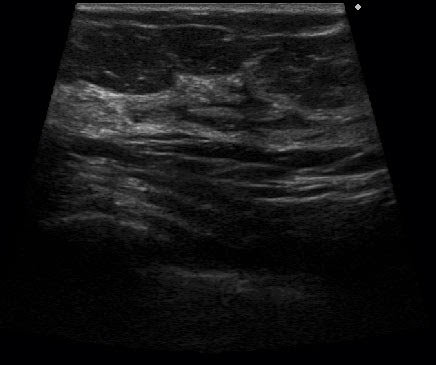

Трапециевидное сканирование (виртуальный конвекс) на линейных датчиках

Благодаря применению данного метода пользователи отказались от особо длинных и неудобных линейных датчиков с апертурой 60 мм и всё чаще выбирают линейные датчики с апертурой около 40 мм как наиболее универсальные с высокой плотностью ультразвуковых лучей.

- Линейный